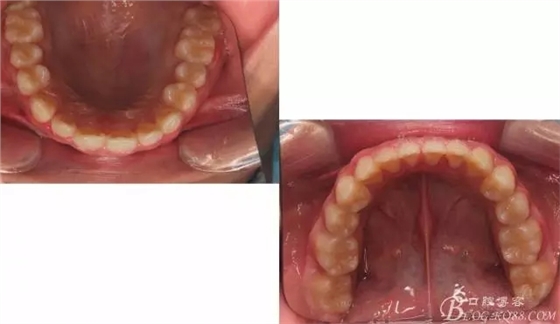

??茩z查:恒牙列,牙列式上下7-7.覆蓋二度,覆合三度,雙側磨牙關系二類,尖牙關系二類,下合3-3各牙間散在約1-1.5mm間隙,輕度唇傾,正面觀顯下頜頦部發(fā)育不足,側貌可觀察到下頜略顯后縮,上頜鼻唇角以及唇部大體正常。開口型向下,舌體正常,TMJ檢查及其它未發(fā)現(xiàn)異常。

佩戴三個月的FR2, 效果奇佳!前牙基本達到淺覆蓋,淺覆合!接下來進入二期直絲弓固定正畸,排齊階段!